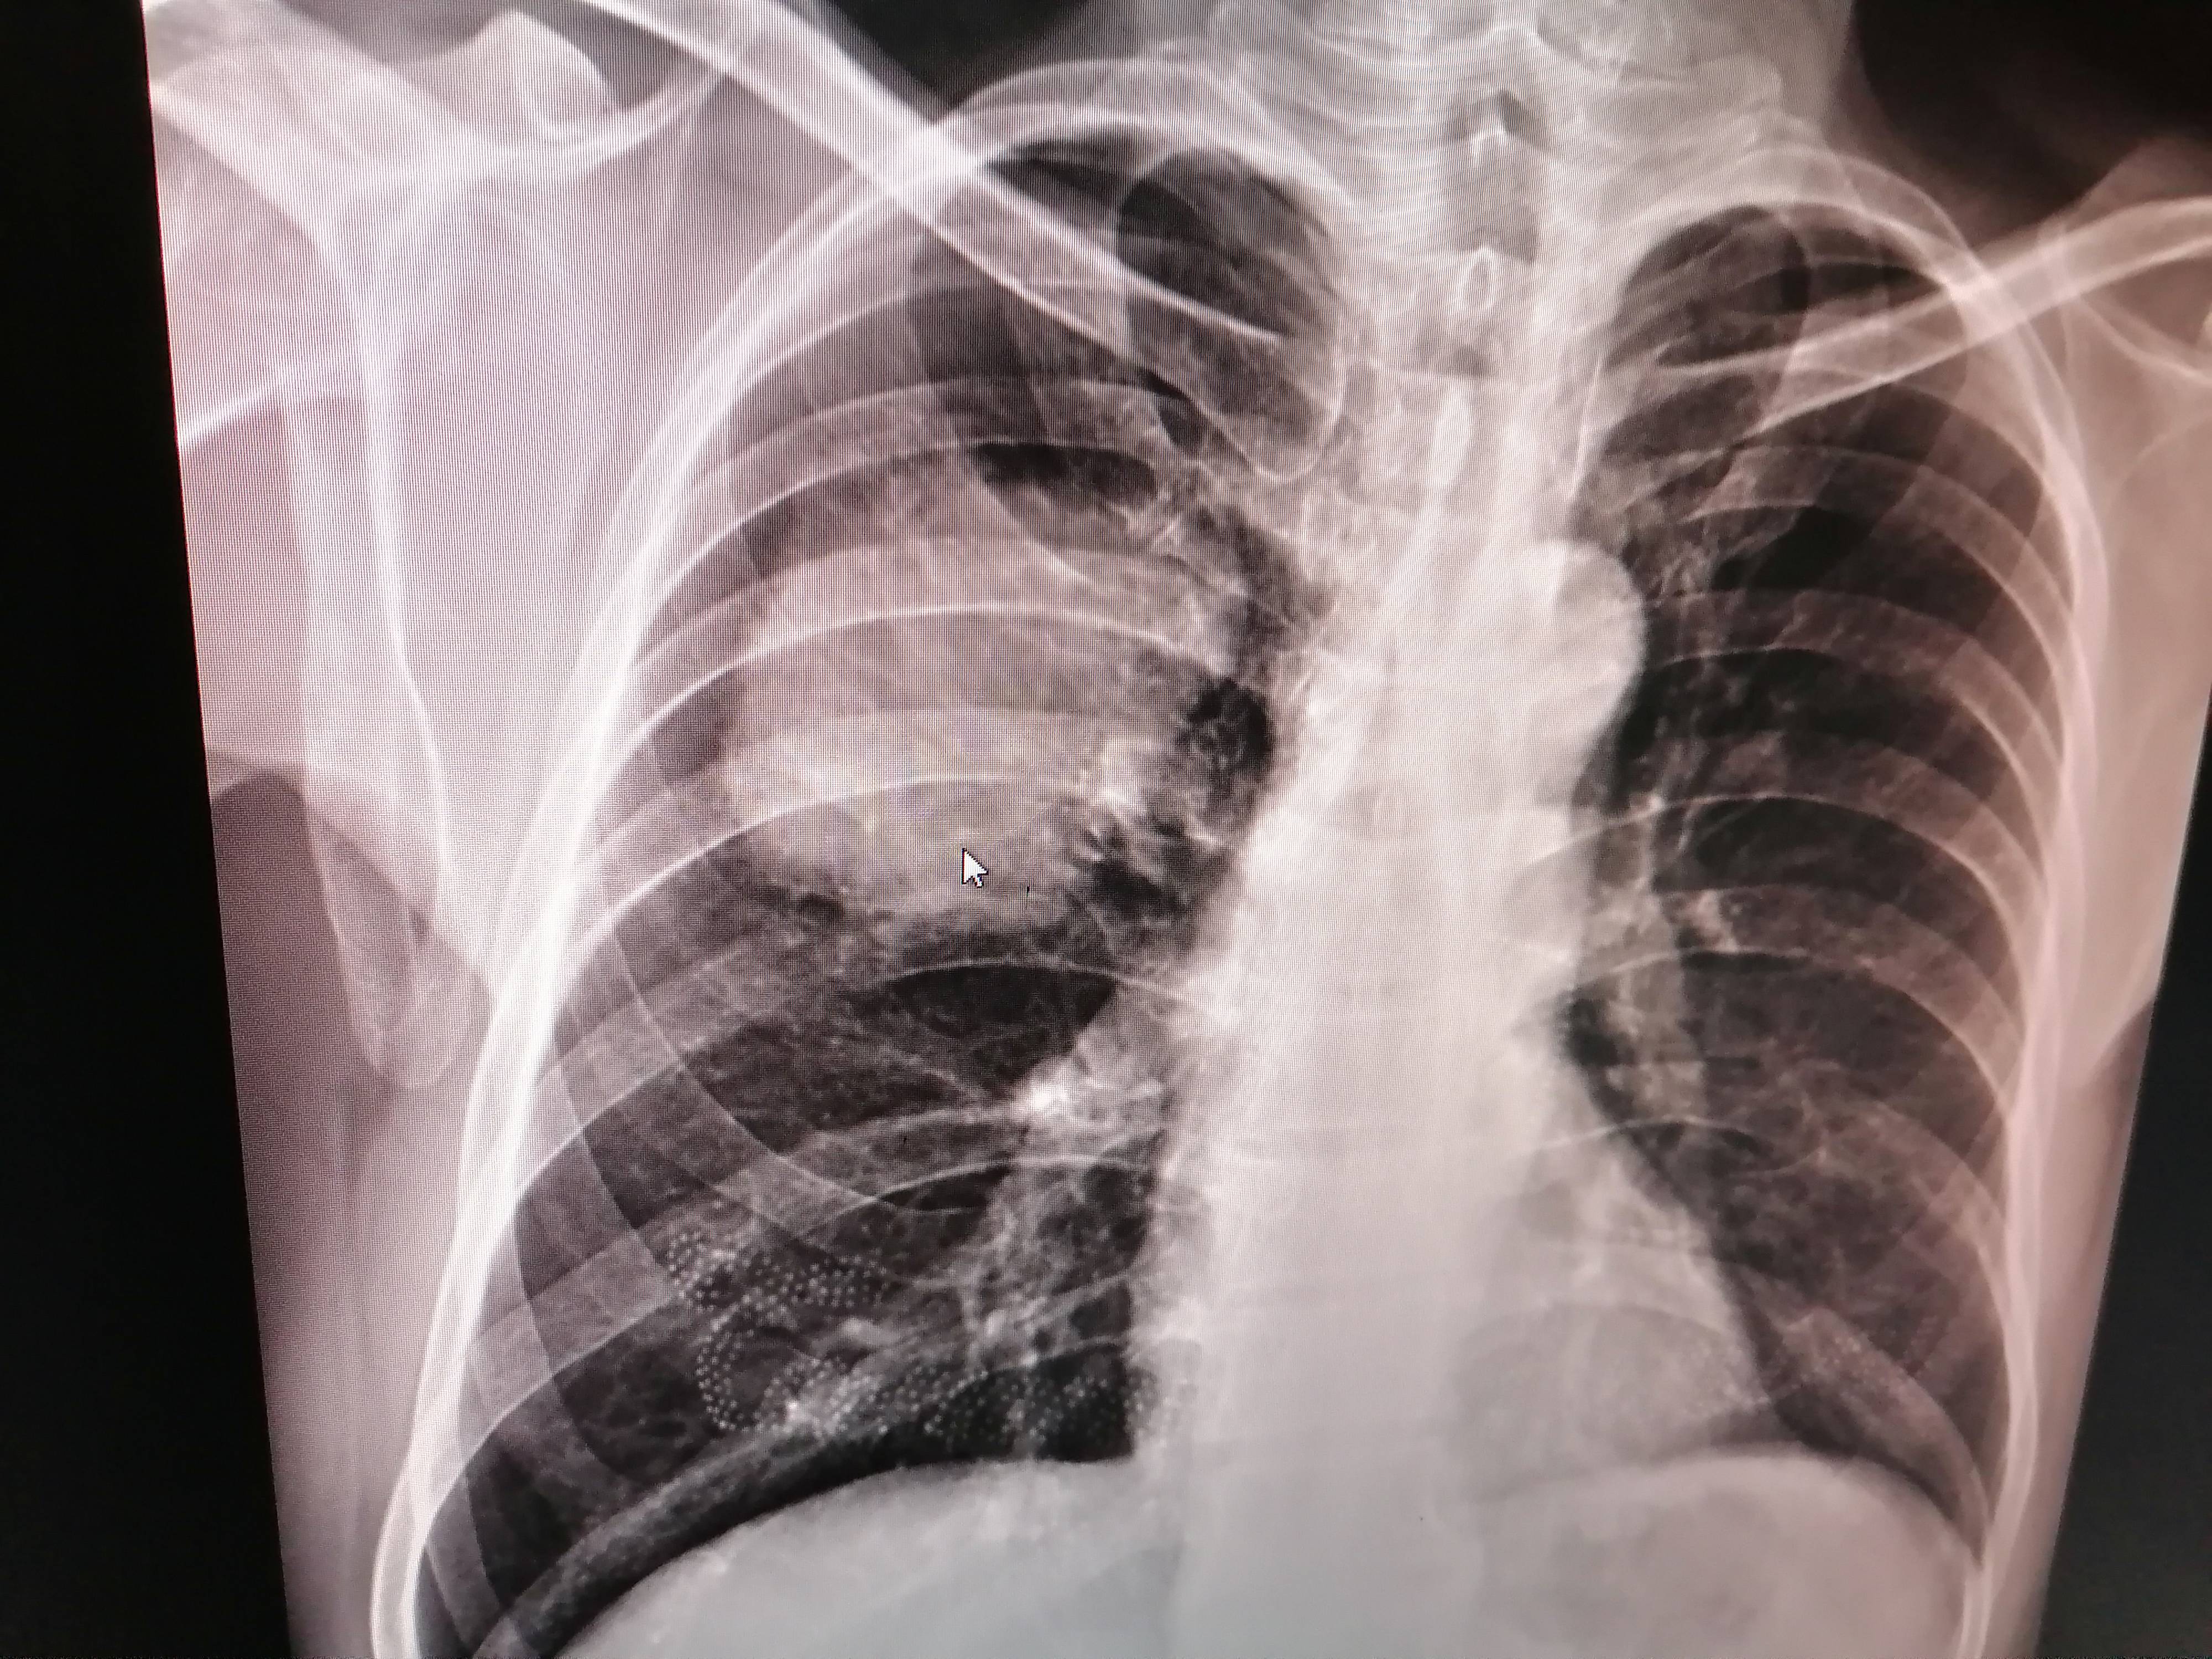

近期复查的报告

主病灶尺寸从最初的7.35*5cm(PET CT报告尺寸),变为目前的2.2*1.6*1.5cm,SUV值1.6。因为SUV值比较低,目前我们不是太担心主病灶。

不过纵隔淋巴结从最初的1.7cm*1.2cm,SUV值4.9.

变更为目前0.9cm,SUV值13.8。这是我们最忧心的一个地方。